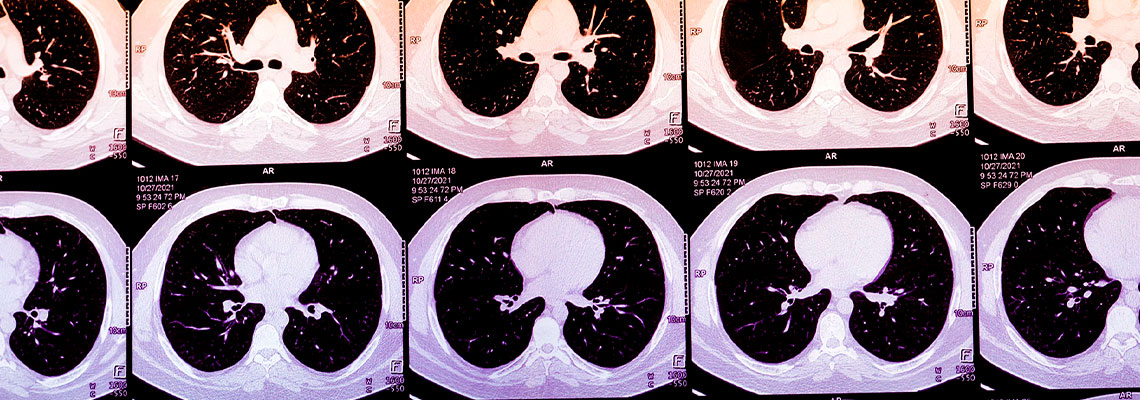

No ano passado, estima-se que 20 milhões de americanos tenham feito tomografias computadorizadas de tórax, após um evento como um acidente de carro ou para rastreio de câncer de pulmão. Frequentemente, elas mostram evidências de cálcio nas artérias coronárias (CAC), um marcador de risco de ataque cardíaco, que fica escondido ou não é mencionado em um laudo de radiologia focado em descartar lesões ósseas, traumas internos com risco de vida ou câncer.

O cálcio em artérias coronárias muitas vezes pode ser visto em tomografias de tórax, e a sua concentração pode ser descrita de forma subjetiva. Normalmente, quantificar o escore de CAC de uma pessoa envolve obter uma tomografia computadorizada específica do coração. Algoritmos que calculam escores de CAC a partir de tomografias de tórax de rotina, porém, poderiam ampliar de forma massiva o acesso a essa métrica. Na prática, esses algoritmos poderiam ser usados para alertar pacientes e seus médicos sobre escores anormalmente altos, incentivando-os a buscar cuidados adicionais. Hoje, a presença das startups que oferecem escores de CAC derivados de IA ainda não é grande, mas está crescendo rapidamente. À medida que o uso aumenta, esses algoritmos podem identificar pacientes de alto risco que tradicionalmente passam despercebidos ou que estão na margem do sistema de cuidados.